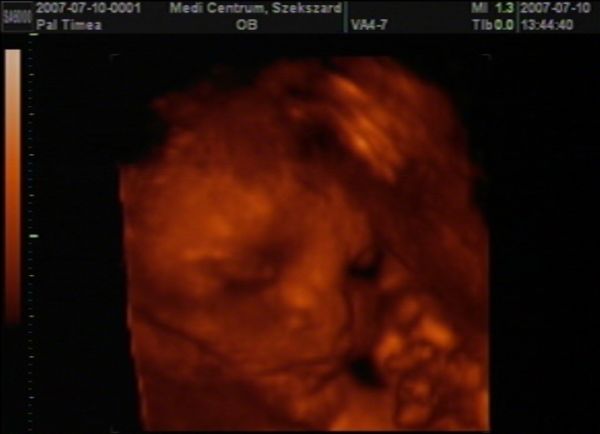

most letömörítettem a 4D-s képünket, remélem sikerül megmutatnom. Kép Olivér 30 hetesen

Kép